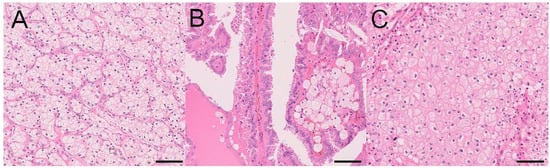

3.1. Clear Cell RCC (CCRCC)

3.2. Papillary RCC (PRCC)

3.3. Chromophobe RCC (ChRCC)